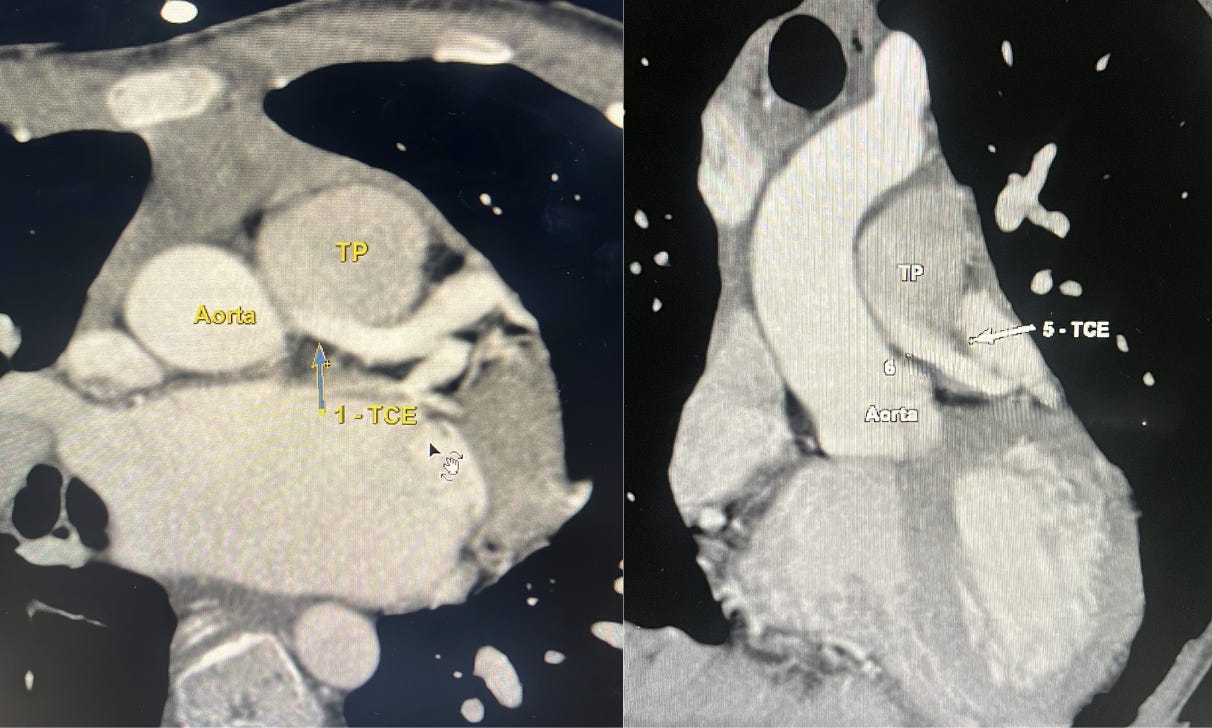

Imagem da semana

Ué, o que está acontecendo com esse Tronco da Coronária Esquerda (TCE)? 🤯

Já ouviu falar em Anomalous origin of the left coronary artery from the pulmonary artery, ou simplesmente ALCAPA, para os íntimos? (nada de confundir com a prima da lhama rs).

Aqui na angioTC dá para ver o detalhe clássico: o TCE não nasce da aorta, mas sim da artéria pulmonar, enquanto a coronária direita surge normalmente da aorta e costuma aparecer bem dilatada, tentando compensar a situação.

O resultado é uma verdadeira “rede de sobrevivência” do miocárdio, com colaterais tortuosas entre os sistemas coronários direito e esquerdo, muitas vezes atravessando o septo interventricular e a superfície epicárdica, aquele padrão exuberante de colaterais que mantém a perfusão em pacientes que sobrevivem até a idade adulta.